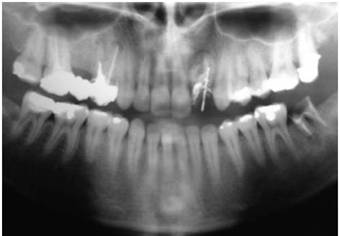

RADIOGRAFÍA PANORÁMICA

Paciente implantado con coronas provisorias en el maxilar superior